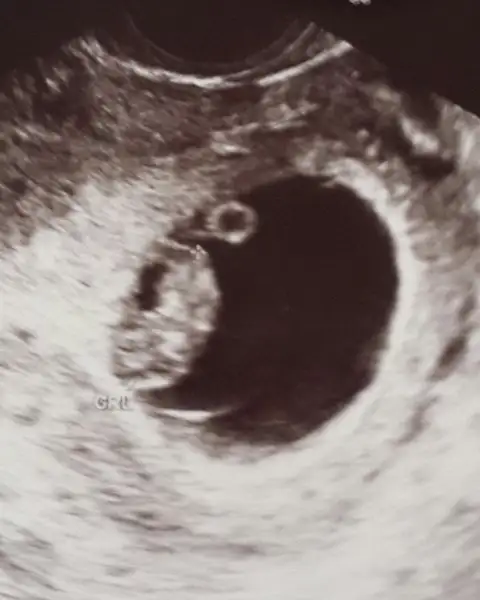

Kizlar benim bebegimede yorum istiyorum :) 8+1

Havalianne__ kizz bude benim bebiki yorumla ikiside vajina yukardaki kizim 8 haftalik adagidaki simdiki 7 haftalik:)) ikisinide yükledim canim kizim erkek di keseye gore ??